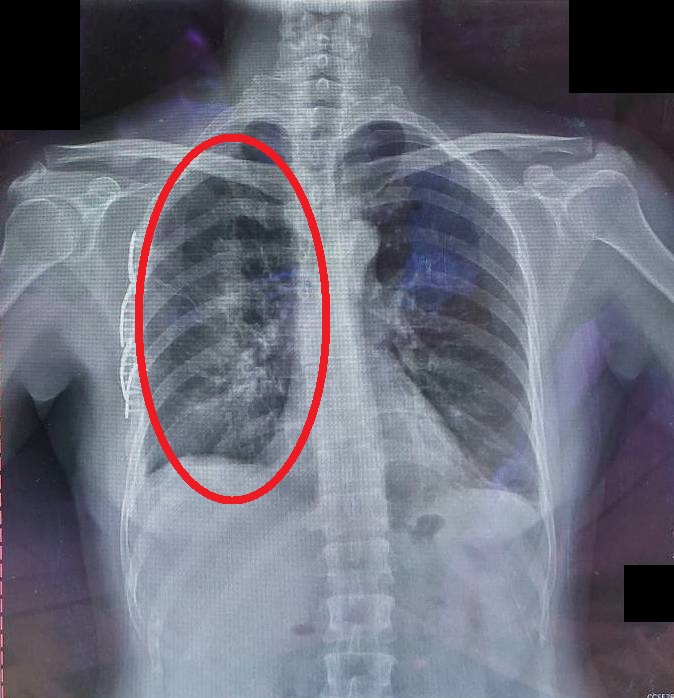

【大紀元2025年04月18日訊】(大紀元記者陳文敏台灣苗栗報導)50歲的賴女士因意外失足跌入深水溝,有呼吸困難、嚴重胸痛的情況,因此緊急送醫。經胸部X光與電腦斷層檢查,發現有多處肋骨骨折,其中部分骨折處產生移位,形成典型的「連枷胸」合併出現肺挫傷與局部塌陷,導致嚴重的呼吸困難。醫療團隊立刻安排微創肋骨骨折固定手術,將骨折的肋骨固定回正確的位置,使胸壁恢復穩定性,改善病人呼吸狀況。

此次案例病人接受微創肋骨骨折固定手術來穩定胸壁,透過鈦合金骨板與螺釘,將骨折的肋骨固定回正確的位置,順利改善呼吸功能。手術後病人的呼吸狀況明顯改善,不再需要高濃度氧氣支持,並逐步接受呼吸復健訓練,術後一週已經能夠下床活動,並在兩週內順利出院。目前門診追蹤顯示,肋骨癒合情況良好,肺部功能也逐漸恢復。